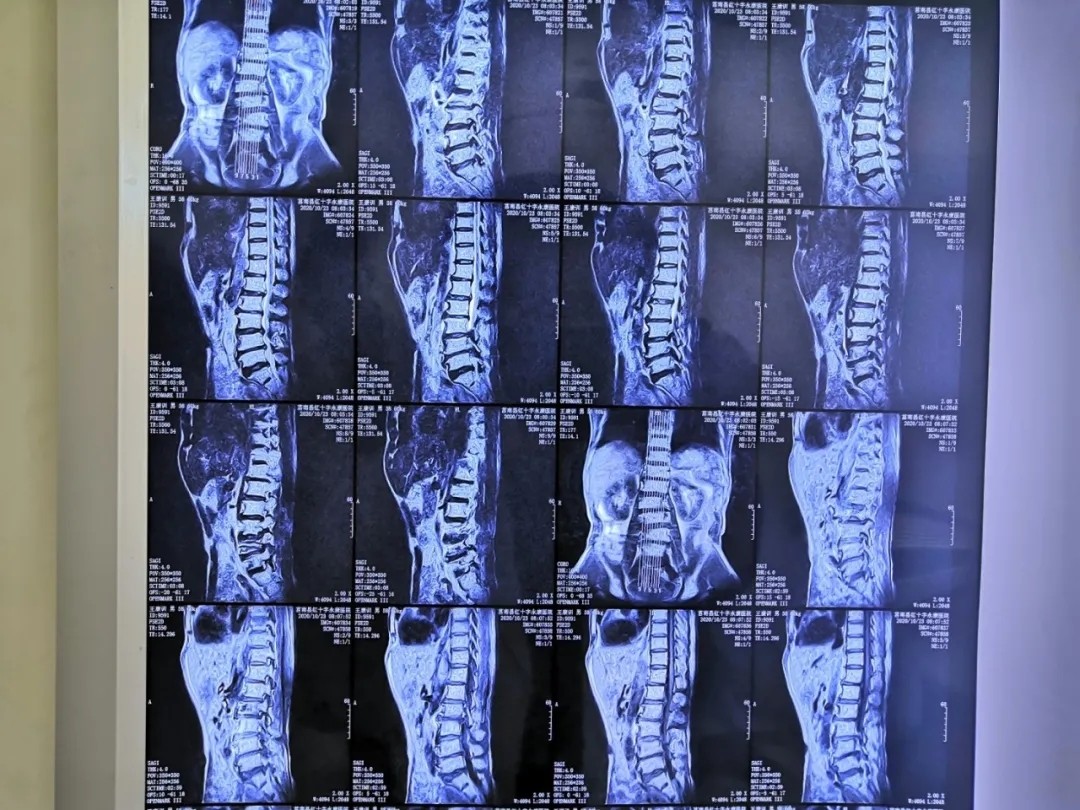

影像资料:

腰椎管狭窄症;腰椎间盘突出症(L4/5);老年退变性侧弯。